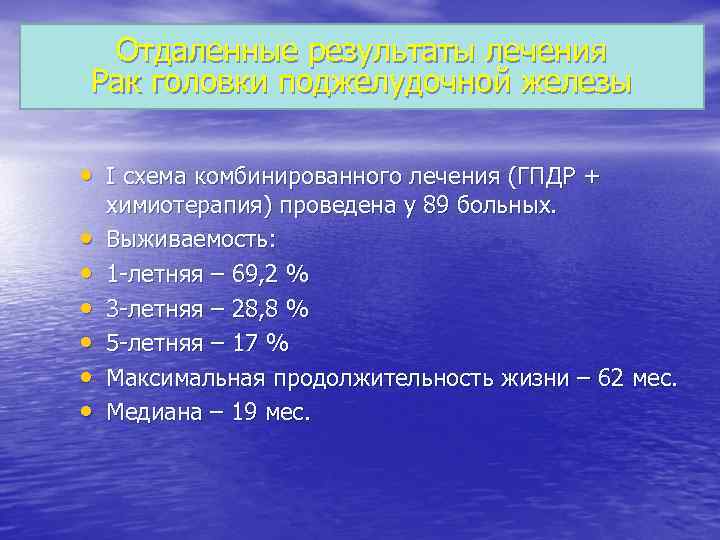

Отдаленные результаты лечения Рак головки поджелудочной железы • I схема комбинированного лечения (ГПДР + • • • химиотерапия) проведена у 89 больных. Выживаемость: 1 -летняя – 69, 2 % 3 -летняя – 28, 8 % 5 -летняя – 17 % Максимальная продолжительность жизни – 62 мес. Медиана – 19 мес.